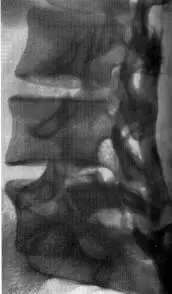

| Спондилолистез 1-й степени (смещение пятого поясничного позвонка кпереди) | Спондилолистез 1-й степени, косая проекция. Определяется незаращение дужки позвонка (диспластический спондилолистез) |

Основным методом в диагностике спондилолистеза, является рентгенография позвоночника в прямой и боковой проекциях. Для решения вопроса состояния дужки смещённого позвонка, рентгенография делается в косой проекции с разными углами ориентации луча, для выявления незаращения дужки позвонка. Для выявления скрытого спондилолистеза (если позвонок смещается только при изменении положения тела или позы) часто применяется рентгенография позвоночника с функциональными пробами. При этом исследовании можно увидеть, в каком положении тела наличествует листез позвонков.